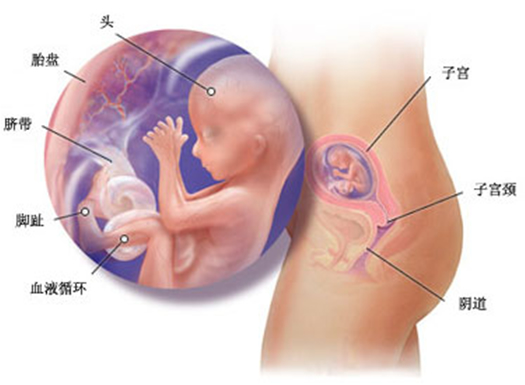

怀孕第 13 周胎儿发育情况

现在胎儿的脸看上去更像成人了,身长大约有 76 毫米,体重比上周稍有增加。他(她)的眼睛在头的额部更为突出,两眼之间的距离拉近了,肝脏开始制造胆汁,肾脏开始向膀胱分泌尿液。

这时你如果用手轻轻在腹部碰触,胎儿就会蠕动起来,但你仍然感觉不到胎儿的动作。 胎儿的神经元迅速地增多,神经突触形成,胎儿的条件反射能力加强,手指开始能与手掌握紧,脚趾与脚底也可以弯曲,眼睑仍然紧紧地闭合。